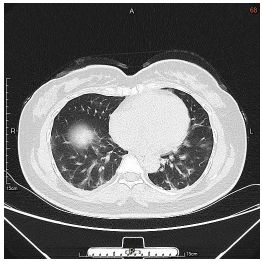

3. This 72-year-old diabetic man was taken to ER for productive cough for 10 days, and rapid progressive dyspnea for 2 days. He also had fever and chill for a week.